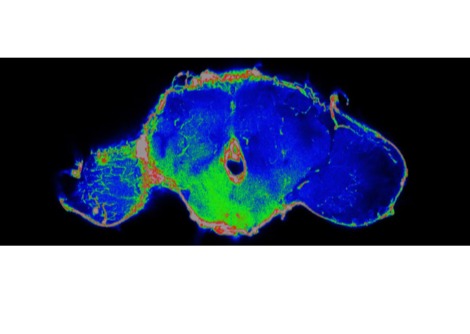

تعتبر اللويحات، وهي كتل خارج الخلية من بروتين AB42 في الدماغ، من العلامات الواضحة لمرض الزهايمر. الخلايا

البلعمية (والتي يشار إليها باسم الخلايا الدبقية الصغيرة عندما تكون موجودة في الدماغ)، وهي خلايا مناعية تبحث عن المواد

غير المرغوب فيها وتدمرها، تزيل AB42 من الدماغ عن طريق تناولها في عملية تسمى البلعمة. في بحث سابق، قام الدكتور

هل يمكن أن تكون هذه البروتيوجليكان على سطح الخلايا بمثابة رابط بين النظام اليومي ومرض الزهايمر؟ وفي سلسلة من

التجارب الأنيقة لاختبار هذه الفرضية، أثبت الفريق أن كمية AB42 التي تبتلعها الخلايا البلعمية السليمة تتذبذب مع إيقاع

الساعة البيولوجية اليومي. ولم يحدث هذا النمط في الخلايا البلعمية التي لا تحتوي على ساعة بيولوجية. كما قاموا بقياس

التذبذبات اليومية في مستويات بروتيوجليكان كبريتات الهيباران وبروتيوجليكان كبريتات الكوندرويتين المنتجة على سطح

الخلايا البلعمية ذات الدورات البيولوجية الصحية. وقد حدث ذروة تصفية AB42 عندما كان إنتاج بروتيوجليكان الخلايا

السطحية في أدنى مستوياته، وأدى إزالة هذه البروتيوجليكان إلى زيادة الابتلاع، مما يشير إلى أن البروتيوجليكان تمنع تصفية

AB42.